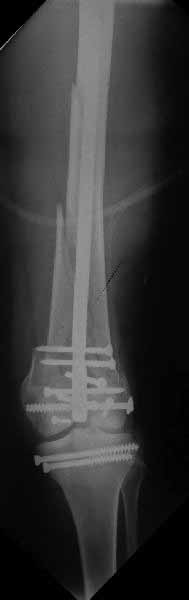

Ответ на эту часть Вашего поста – вложенный файл. Больная оперирована неделю назад по поводу открытого перелома дистального эпиметафиза бедренной кости. После операции она идёт в рентгенкабинет для выполнения послеоперационной контрольной рентгенографии, представленной на слайдах 10 и 11. Узнав, почему её фотографируют, просила передать Вам, Антон, привет.

И уже лет шесть мы используем возможность ввести в дистальное овальное отверстие 3 винта, которые именно запираются в этом отверстии, не люфтят, а обеспечивают угловую стабильность - см картинку.

Получается и стабильно, и очень дистально, нижний край отверстия в 3 мм от дистального конца гвоздя.

В приложении пример недавней операции, C3, открытая репозиция, фиксация мыщелков спицами и винтами, ретроградный синтез большеберцовым гвоздем 10,5 мм диаметром, винты 5 мм.